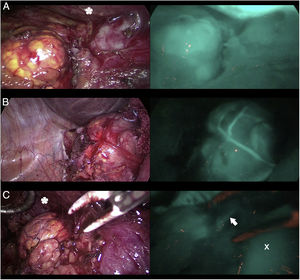

DiscussionThe use of ICG in endocrine surgery is a safe and effective technique. The recommended dose is 5mg, both in adrenal and thyroid surgery, although its administration can be repeated on several occasions, if necessary. In the field of adrenal surgery (Fig. 1), ICG shows clear adrenal hyperfluorescence in the first minute, maximum after 5min and visible up to 20min after infusion, which allows it to be perfectly differentiated from the surrounding fatty tissue and ensure its dissection and complete resection. In addition, the visualization of adrenal vascularization with ICG, although inconstant, can provide greater control during dissection maneuvers and thus reduce the rates of hemorrhagic complications, as well as those derived from glandular manipulation. It is worth mentioning that tumors of the adrenal cortex appear to be hyperfluorescent, while spinal tumors and malignant tumors would be hypofluorescent compared to the rest of the gland, which is of special interest in partial resections. Similarly, the use of ICG in cervical endocrine surgery (Fig. 2) shows a parathyroid fluorescence clearly superior to the thyroid and visible from 30 to 60s to 20min after infusion. Young age, high levels of preoperative calcemia and a high glandular size could correlate with greater parathyroid hyperfluorescence. There is also an interesting correlation between hyperfluorescence and postoperative parathyroid function. The presence of at least one well-vascularized parathyroid gland could avoid postoperative hypofunction, and postoperative follow-up lab tests and prophylactic treatment may be unnecessary. Several subjective scales have been developed to measure parathyroid fluorescence with promising results, but there are still few methods for objective intraoperative grading. The discovery of parathyroid autofluorescence (Fig. 3), without the need for the administration of any exogenous tracer, and clearly superior to the thyroid, presents an important change in the field of fluorescence-guided endocrine surgery. Parathyroid autofluorescence is not related to glandular function, vascularization, or disease. Secondary hyperparathyroidism, high BMI, high serum calcium levels and low preoperative vitamin D levels have been associated with lower autofluorescence, with no differences according to age, sex, ethnicity or preoperative PTH levels. This technique seems to have a similar rate of parathyroid identification as ICG, but it provides faster glandular detection and may help reduce the rate of postoperative hypocalcemia.

Three cases (A, B and C) of anterior laparoscopic adrenalectomy with Karl Storz® Image 1 HD device. In the left column, the adrenal glands are illuminated with white light and in the right column under NIR light after infusion of 5mg of intravenous ICG. Adrenal hyperfluorescence was observed in all 3 cases, clearly greater than in the surrounding fatty tissue. The white arrow indicates the right suprarenal vein. Hepatic hyperfluorescence is marked with *. The inferior vena cava is marked with an X.